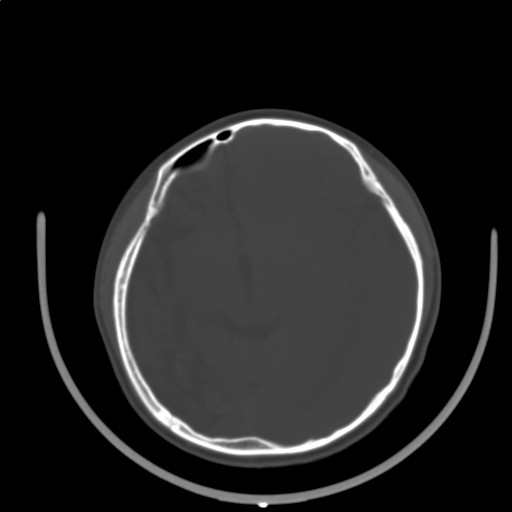

标题: PED3416:F,12Y,智力下降,学习成绩差,8个月时发过高烧。

右侧半球萎缩,软化,多量脑回样钙化,考虑颅面血管瘤病,建议dsa检查

右侧半球萎缩,软化,多量脑回样钙化,同侧颅盖板障增宽,考虑颅面血管瘤病,建议dsa检查与化脓性脑膜炎后遗改变鉴别。